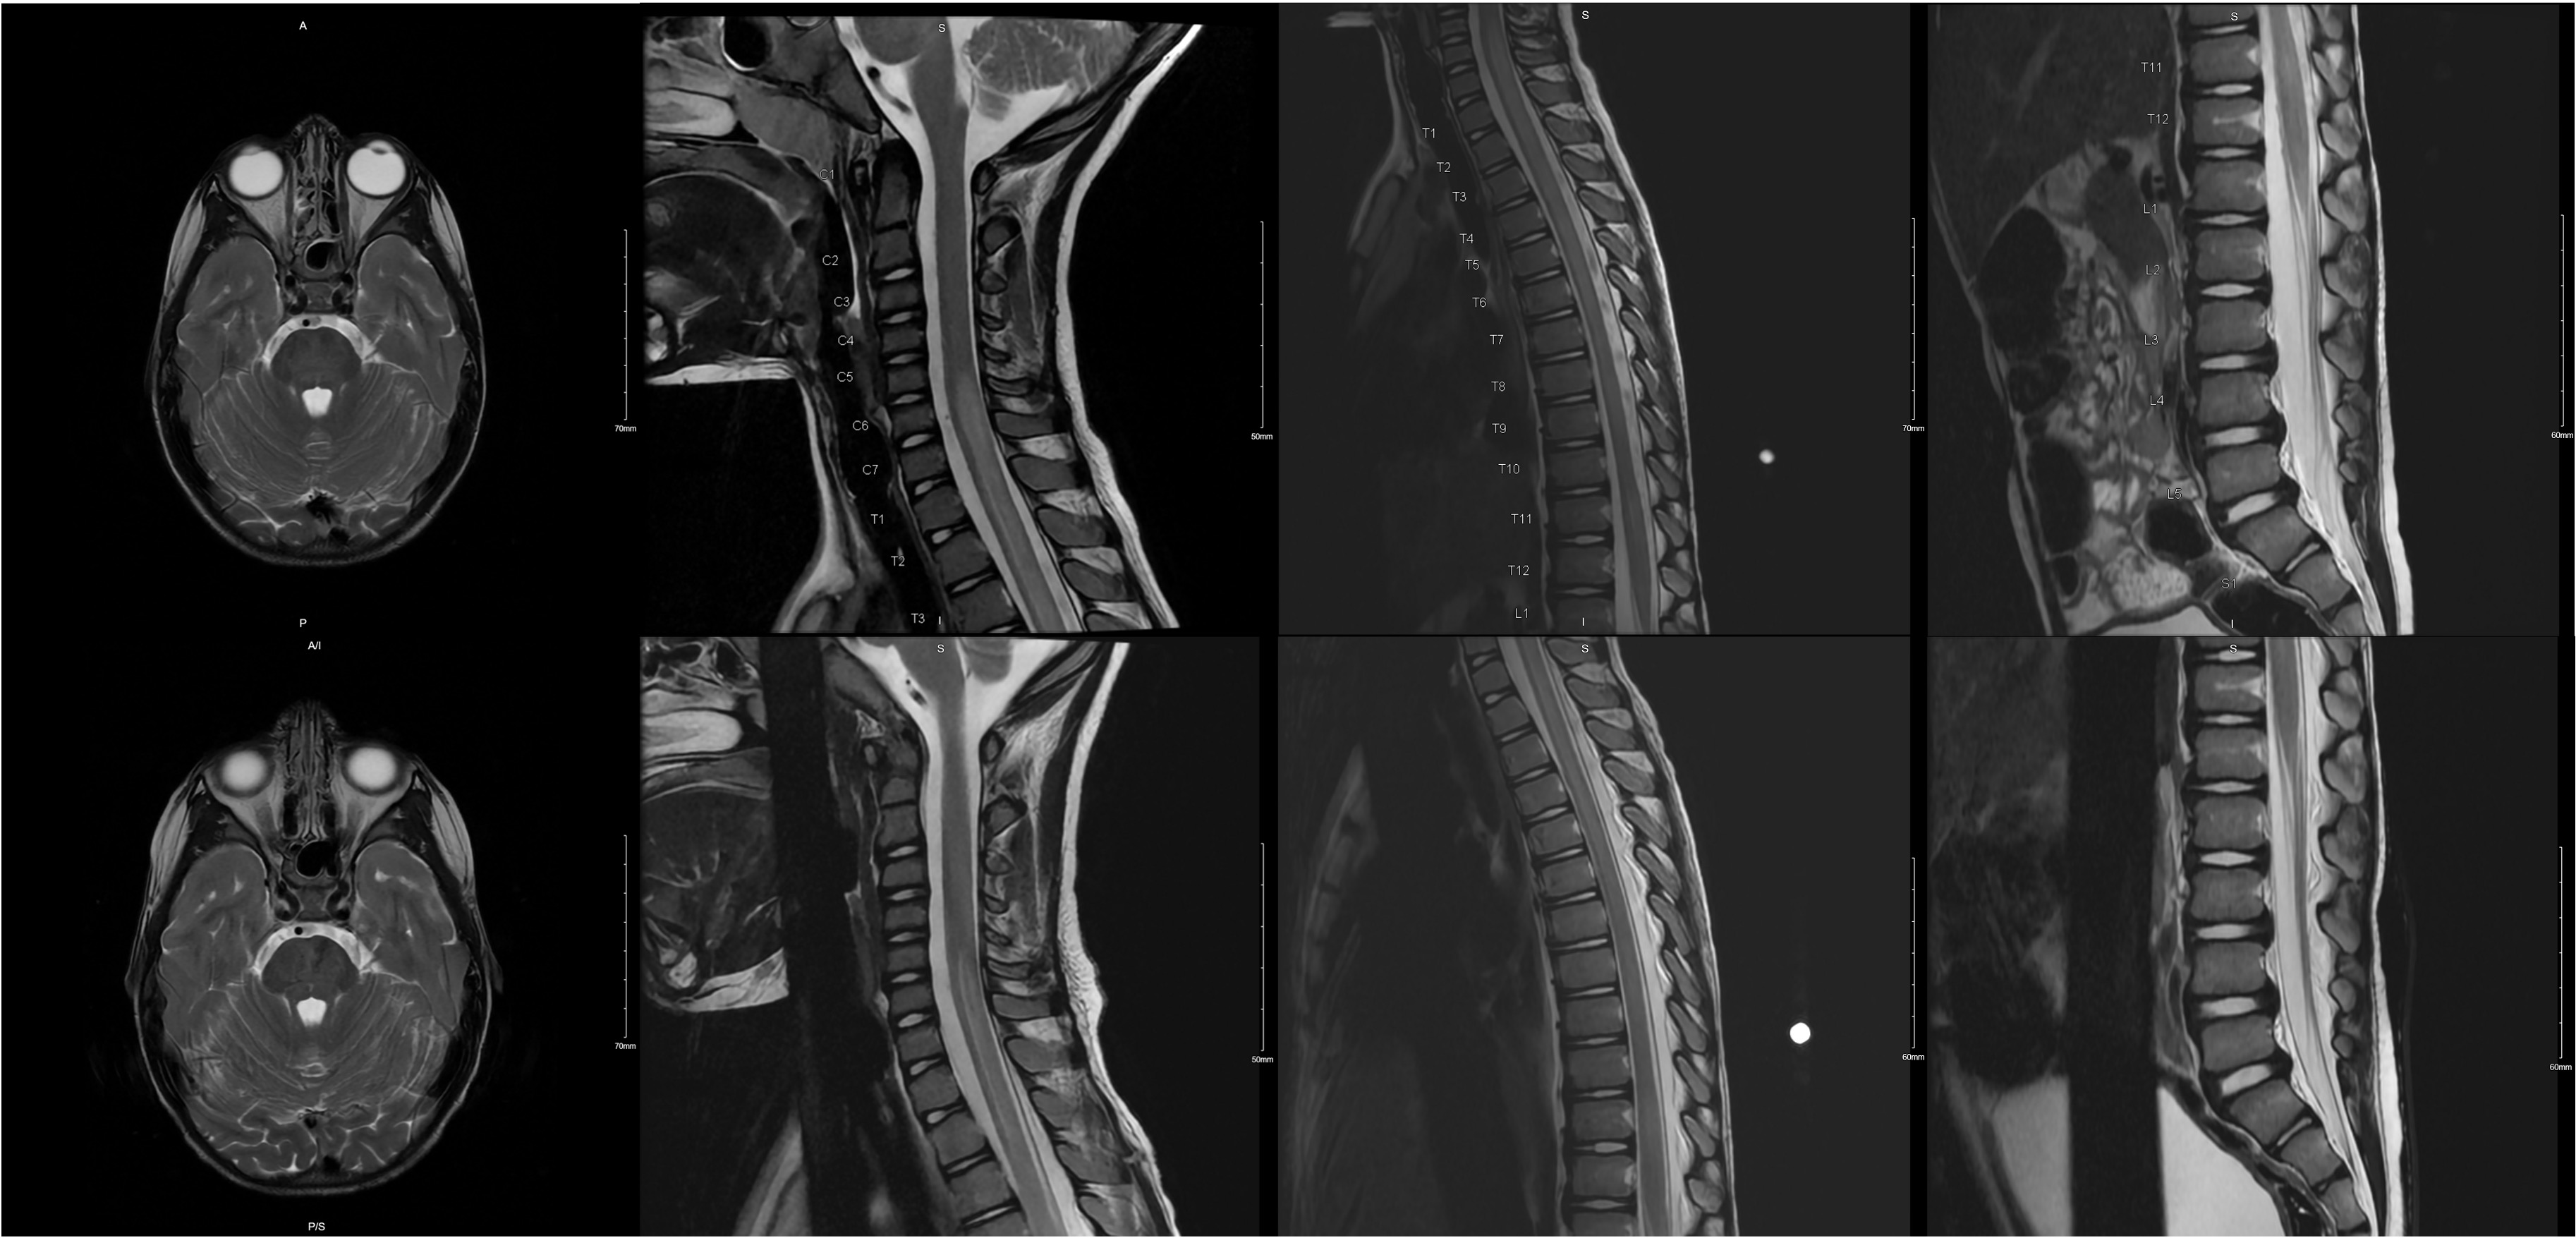

步态障碍在儿科患者可以与广泛的感染性,创伤性,肌肉骨骼和神经学的病因诊断陷阱。此外,孩子们可能很难表达他们的痛苦,也很难检查。这个病例强调了慢下来获取详细病史以及对我们的儿科患者进行彻底检查的重要性,这在繁忙的急诊科可能是具有挑战性的。我们提出一个病例急性横断脊髓炎(ATM)在一个四岁的男性谁提出了一天的跛行和双侧腿痛与负重。看护人报告说可能是日托所里的斗殴造成的远端创伤。神经学检查显示明显异常,包括双侧髌骨反射亢进、双侧下肢无力、阵挛和步态失调。脑和脊柱MRI显示纵向广泛的ATM伴脊髓水肿。尽管缺乏感染前驱症状的证据,但脑脊液感染分析显示肺炎支原体是病原体。静脉注射(IV)甲基强的松龙和阿奇霉素治疗导致出院后几周内所有神经系统后遗症的最终解决。本报告强调了在鉴别以步态疾患为表现的儿科患者时考虑ATM的重要性,以及彻底的神经学检查的重要性,否则诊断将被错过。主题:小儿急诊医学、小儿神经病学、急性横断面脊髓炎、小儿步态障碍。

Gait disturbances in pediatric patients can be wrought with diagnostic pitfalls given the broad infectious, traumatic, musculoskeletal, and neurological etiologies. Furthermore, children can have difficulty communicating their pain and can be hard to examine. This case highlights the importance of slowing down to obtain a detailed history as well as perform a thorough exam in our pediatric patients, which can be challenging in a busy emergency department. We present a case of acute transverse myelitis (ATM) in a four-year-old male who presented with a one-day history of limp and bilateral leg pain with weight bearing. The caretakers reported a possible remote trauma from roughhousing at daycare. Neurological examination revealed significant abnormalities including bilateral patellar hyperreflexia, bilateral lower extremity weakness, clonus, and gait ataxia. A brain and spinal MRI revealed longitudinally extensive ATM with cord edema. Despite the lack of any evidence of infectious prodrome, cerebrospinal infectious analysis revealed Mycoplasma pneumonia as the causative agent. Treatment with intravenous (IV) methylprednisolone and azithromycin therapy led to eventual resolution of all neurological sequelae within a few weeks of discharge. This report emphasizes the importance of considering ATM in the differential of pediatric patients presenting with gait complaints, as well as the importance of a thorough neurologic exam, without which the diagnosis would have been missed.